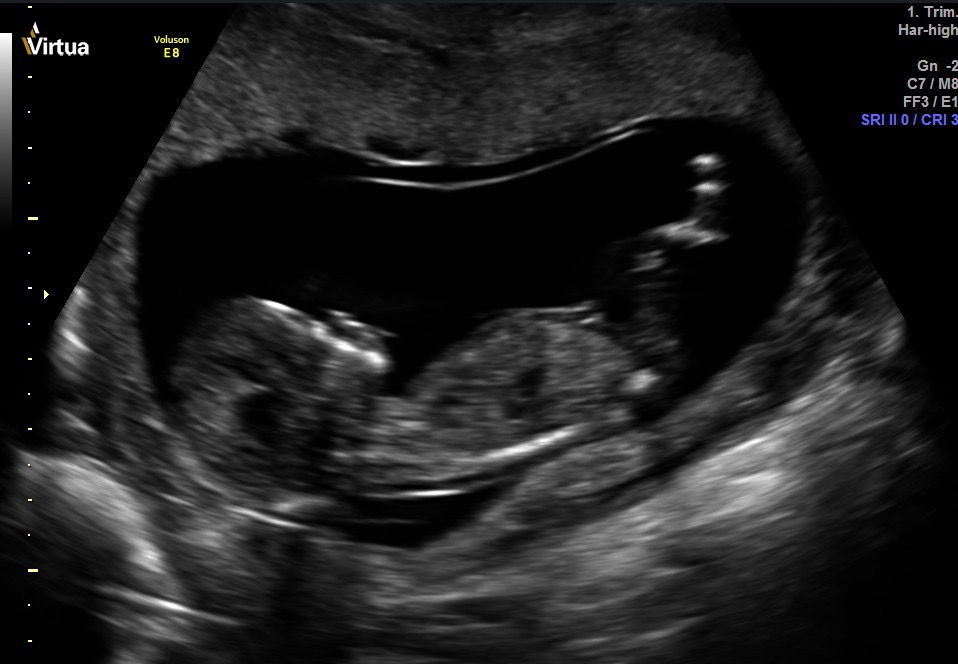

I don't see a nub, but I'm terrible at looking at these things. Can anyone guess the gender? Thank you for your help! I will come back and update on Thursday since we are going for a private scan. Hopefully baby cooperates!Attachment 34055Attachment 34056Attachment 34057Attachment 34061